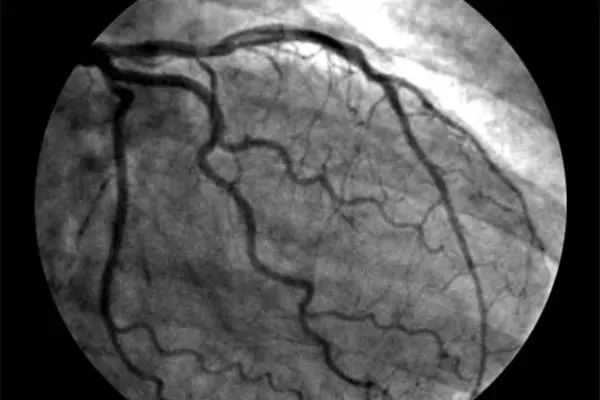

什么是冠状动脉造影?

冠状动脉造影是诊断冠状动脉粥样硬化性心脏病(冠心病)的一种常用而且有效的方法 , 是一种较为安全可靠的有创诊断技术 , 现已广泛应用于临床 , 被认为是诊断冠心病的“金标准” 。